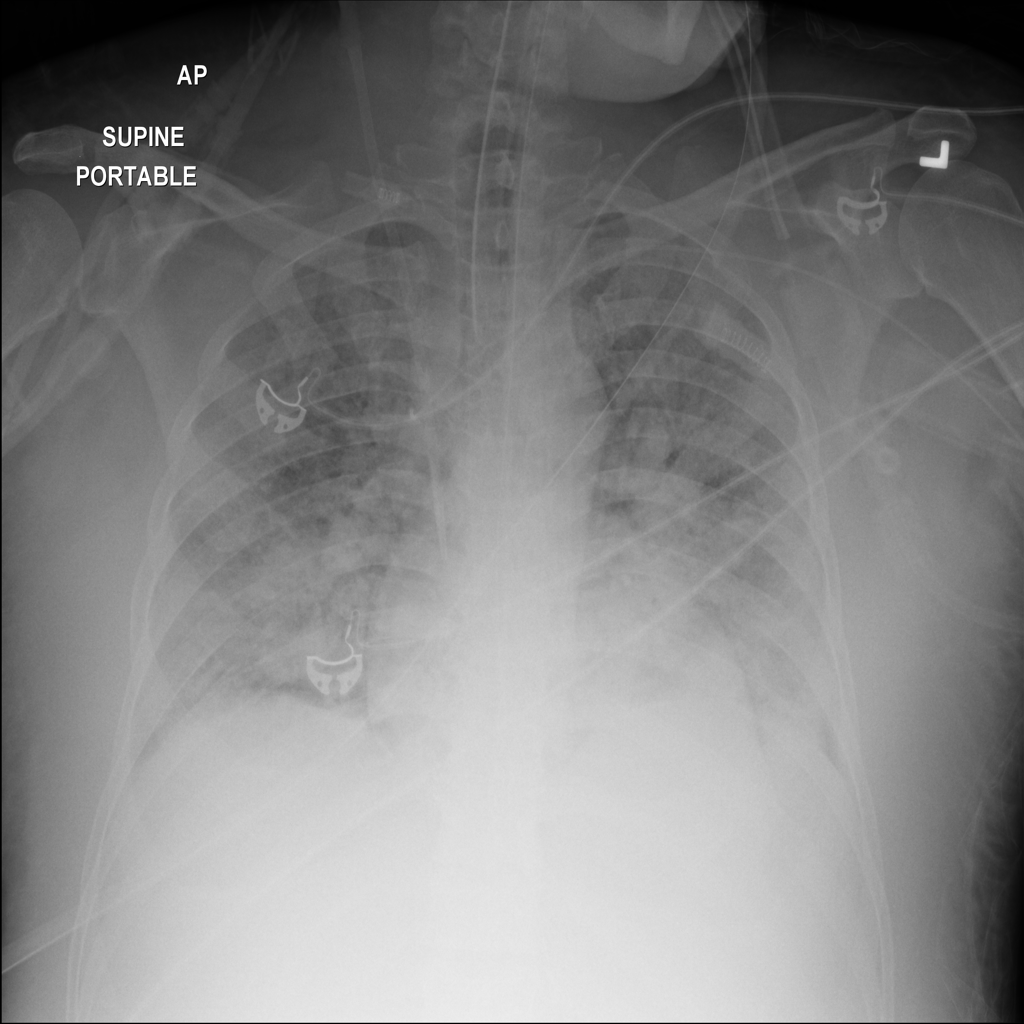

Mass

A mass is a larger focal opacity or lesion seen on the image. It is a descriptive finding that can have several causes and usually needs more imaging or clinical context to characterize.

PAT-4639 · IMG-024Mass

PAT-4639 · IMG-024

AP